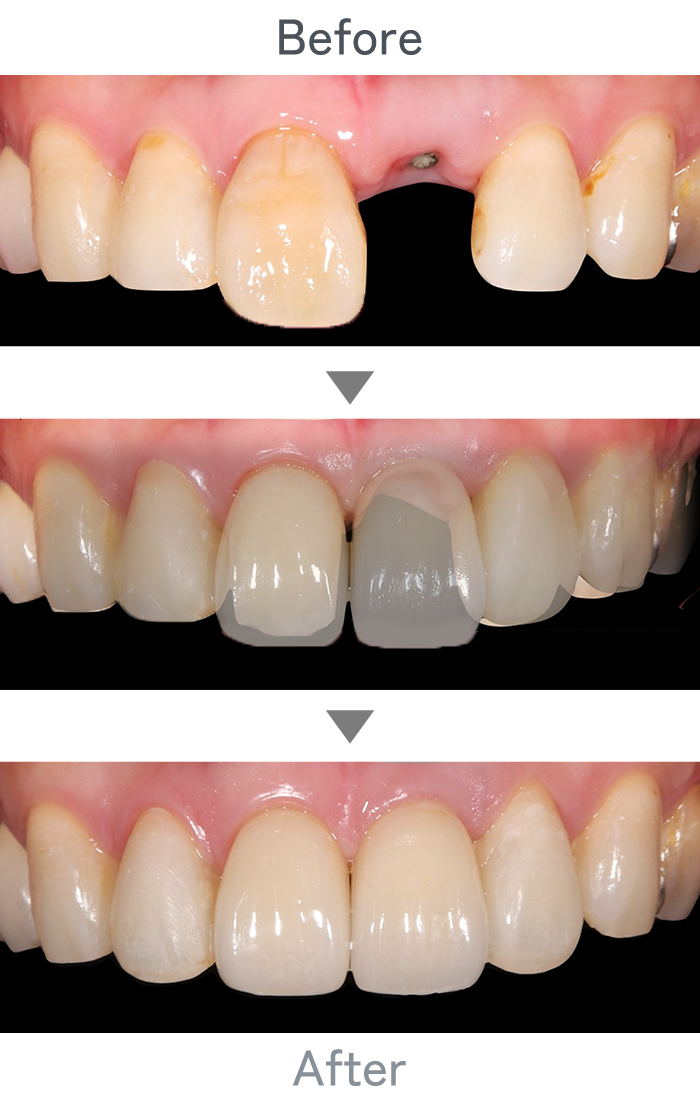

インプラント治療

+

ラミネートべニア

前歯のインプラント

主訴 前歯折れた

治療法 左上1番:インプラント治療

右上1番:ラミネートべニア

治療期間 4ヶ月半

費用 ・インプラント左上1番:300,000円

・インプラント左上1番上部構造:120,000円

・ラミネートべニア右上1番:100,000円

小 計:520,000円

消費税:52,000円

合 計:572,000円

※インプラント体、上部構造ともに『10年保証』

副作用

• メンテナンスが必要